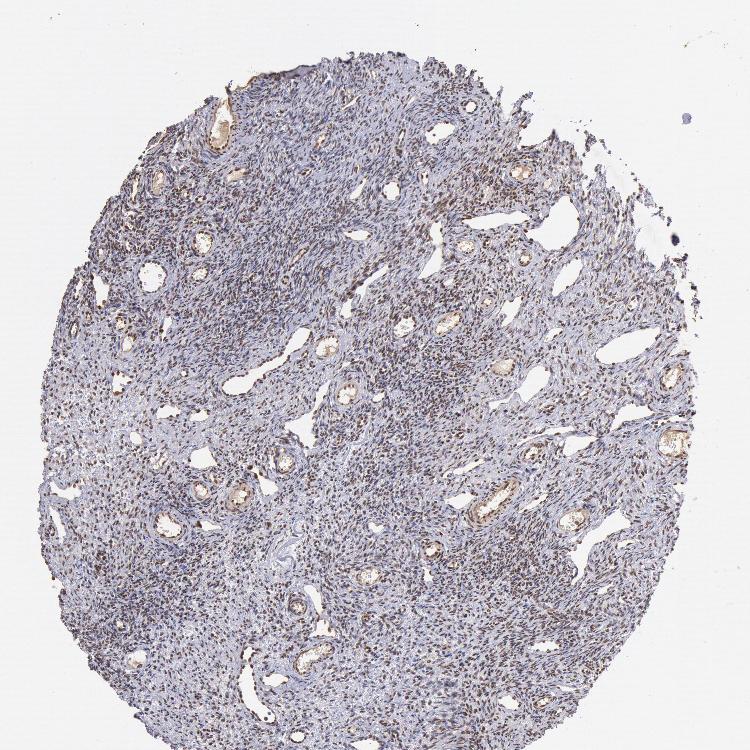

CDKN2B